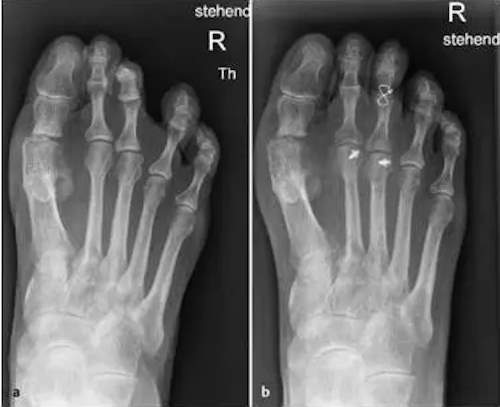

Brachmetatarsie = Verkürzung eines Mittelfußstrahls kann zu einer Metatarsalgie führen

Komplexe Vorfußkorrektur bei Metatarsalgie II und III: Verkürzende Osteotomie der Mittelfußknochen II und III durch eine Weil Osteotomie